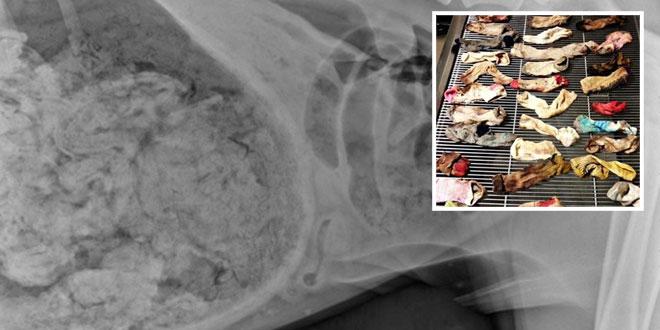

നായ്ക്കുട്ടിയുടെ വയറ്റിൽ നിന്നും 43 സോക്‌സുകൾ പുറത്തെടുത്തു

ന്യൂയോർക്ക് :  നായ്ക്കുട്ടിയുടെ വയറ്റിൽ നിന്നും  43 സോക്‌സുകൾ പുറത്തെടുത്തു .അമേരിക്കയിലെ പോർട്ട്‌ലാന്റിലാണ് സംഭവം നടന്നത് .ഗ്രേറ്റ് ഡെയ്ൻ എന്ന മൂന്ന് വയസ്സുപ്രായമുള്ള നായക്കുട്ടിയുടെ വയറ്റിൽ നിന്നാണ് സോക്സുകൾ പുറത്തെടുത്തത്.ഓക്കാനവും മറ്റ് ശാരീരിക അസ്വസ്ഥതകളും കണ്ടതിനെ തുടർന്നാണ് ഉടമസ്ഥൻ അതിനെയും കൊണ്ട് മൃഗാശുപത്രിയിലെത്തിയത്. ഡോക്ടർമാർ എക്‌സ-റേ എടുത്ത് പരിശോധിച്ചപ്പോൾ നായ്ക്കുട്ടിയുടെ വയറ്റിൽ എന്തൊക്കെയോ സാധനങ്ങൾ കിടക്കുന്നത് കണ്ടു. പിന്നീട് ശസ്ത്രക്രിയക്ക് വിധേയനാക്കിയപ്പോഴാണ് ഡോക്ടർമാർ ശരിക്കും ഞെട്ടിയത്. തുടർന്ന് രണ്ട് മണിക്കൂർ നീണ്ട ശസ്ത്രക്രിയയ്‌ക്കൊടുവിലാണ് 43 സോക്സുകൾ പുറത്തെടുത്തത് . .ഇത്തരം ഒരു സംഭവം ചരിത്രത്തിലേ ഉണ്ടായിരികാനിടയില്ലെന്ന് ശസ്ത്രക്രിയയ്ക്ക് നേതൃത്വം നൽകിയ ഡോ.ആഷ്‌ലി മാഗി പറഞ്ഞു. ഡോക്ടർമാരുടെ കണക്ക് പ്രകാരം നാൽപ്പത്തി മൂന്നര സോക്‌സാണ് നായ്ക്കുട്ടി വയറ്റിലാക്കിയത്.ശസ്ത്രക്രിയയ്ക്ക് ശേഷം ഒരു ദിവസത്തിന് ശേഷം ഗ്രെയ്റ്റ് ഡെയ്ൻ ആശുപത്രി വിട്ടു.